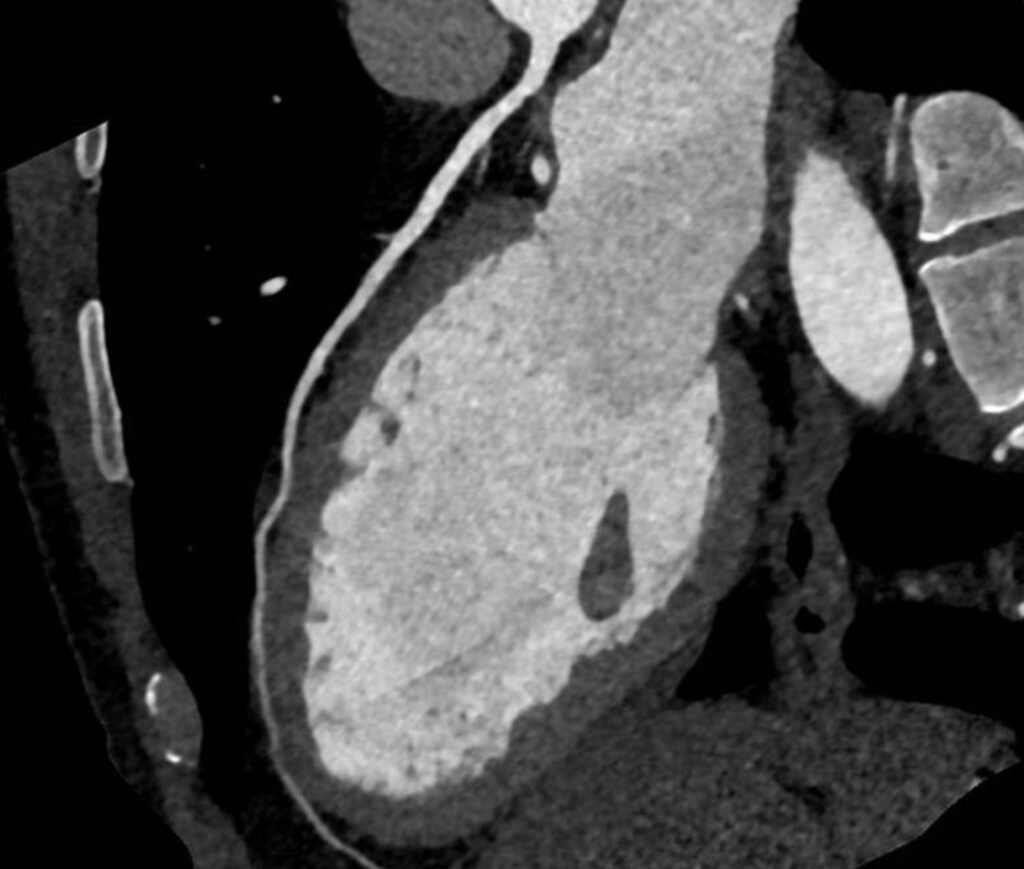

1150 Slice CT Scan

A first in India and Asia, this ultra-fast high-resolution CT scanner provides detailed cross-sectional images of the heart and blood vessels. Ideal for cardiac imaging, it captures precise anatomical data with low radiation exposure. Enabling over 100 CT scans in 1 day, giving more patients quicker results and diagnosis with help of advanced technology.